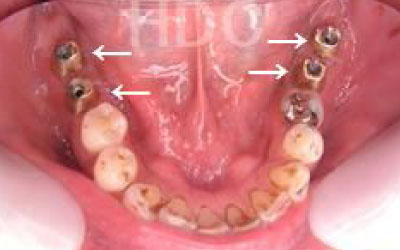

1人の歯科医師の視点でなく、複数のドクターでCTの診断や計画を立てています。

CTでは、骨や歯の状態を三次元で確認でき、正確な距離を測定することができます。

骨の厚さや傾き、神経の位置などを事前に詳しく計測することで、安全にインプラントを行うことができます。

しかし、事前にCTでしっかりと撮影し、三次元的に神経との距離を計測して治療計画を立てることで、心配は不要です。

また、当院では削りすぎを防ぐためのストッパーも使用しています。